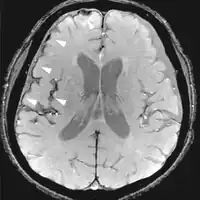

Diffusion weighted (DWI)ConventionalDWIMeasure of Brownian motion of water molecules.[26] High signal within minutes of cerebral infarction (pictured).[27]